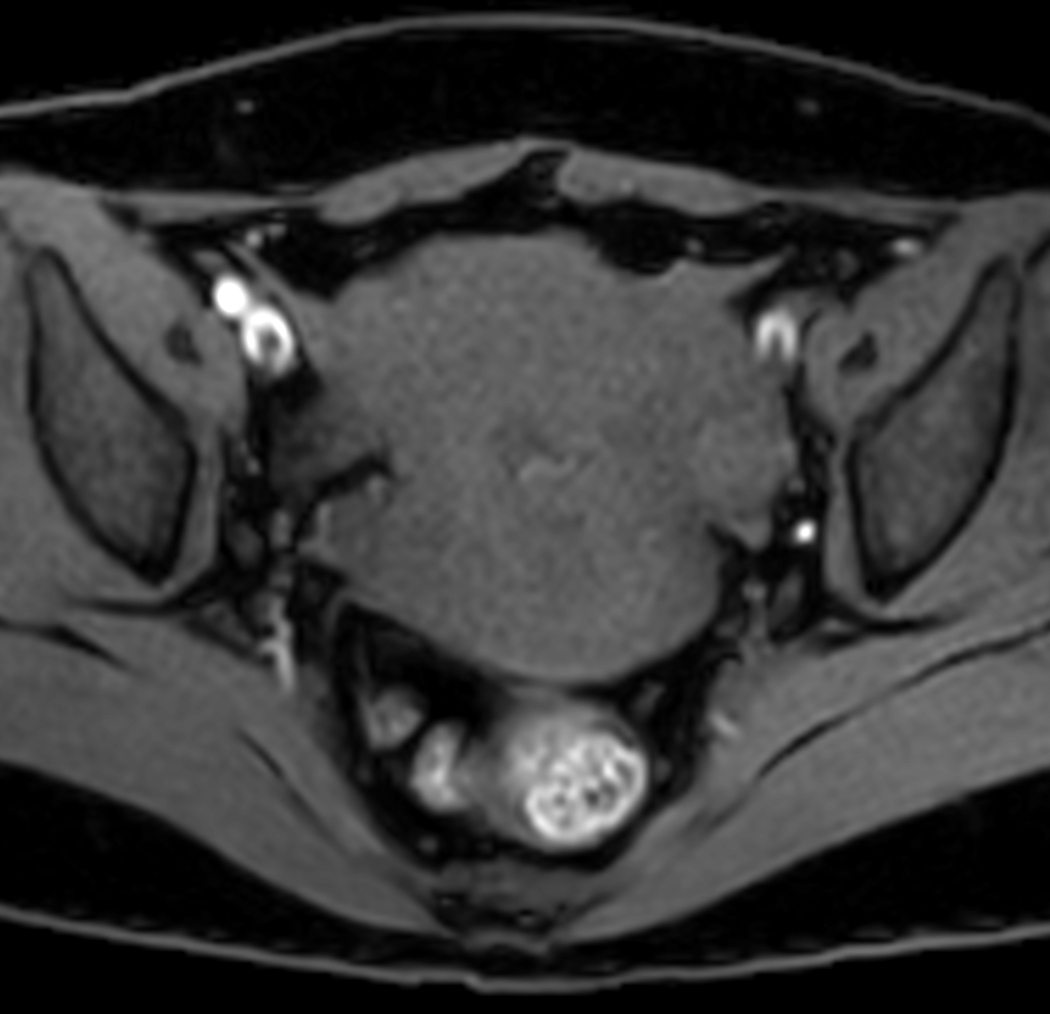

Axial mDIXON XD - T1w FFE (Water only)